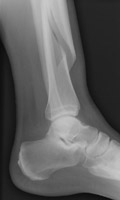

- Click on the image for a larger versionBLateral radiograph of the tibia and fibula. This demonstrates a spiral fracture of the tibia.